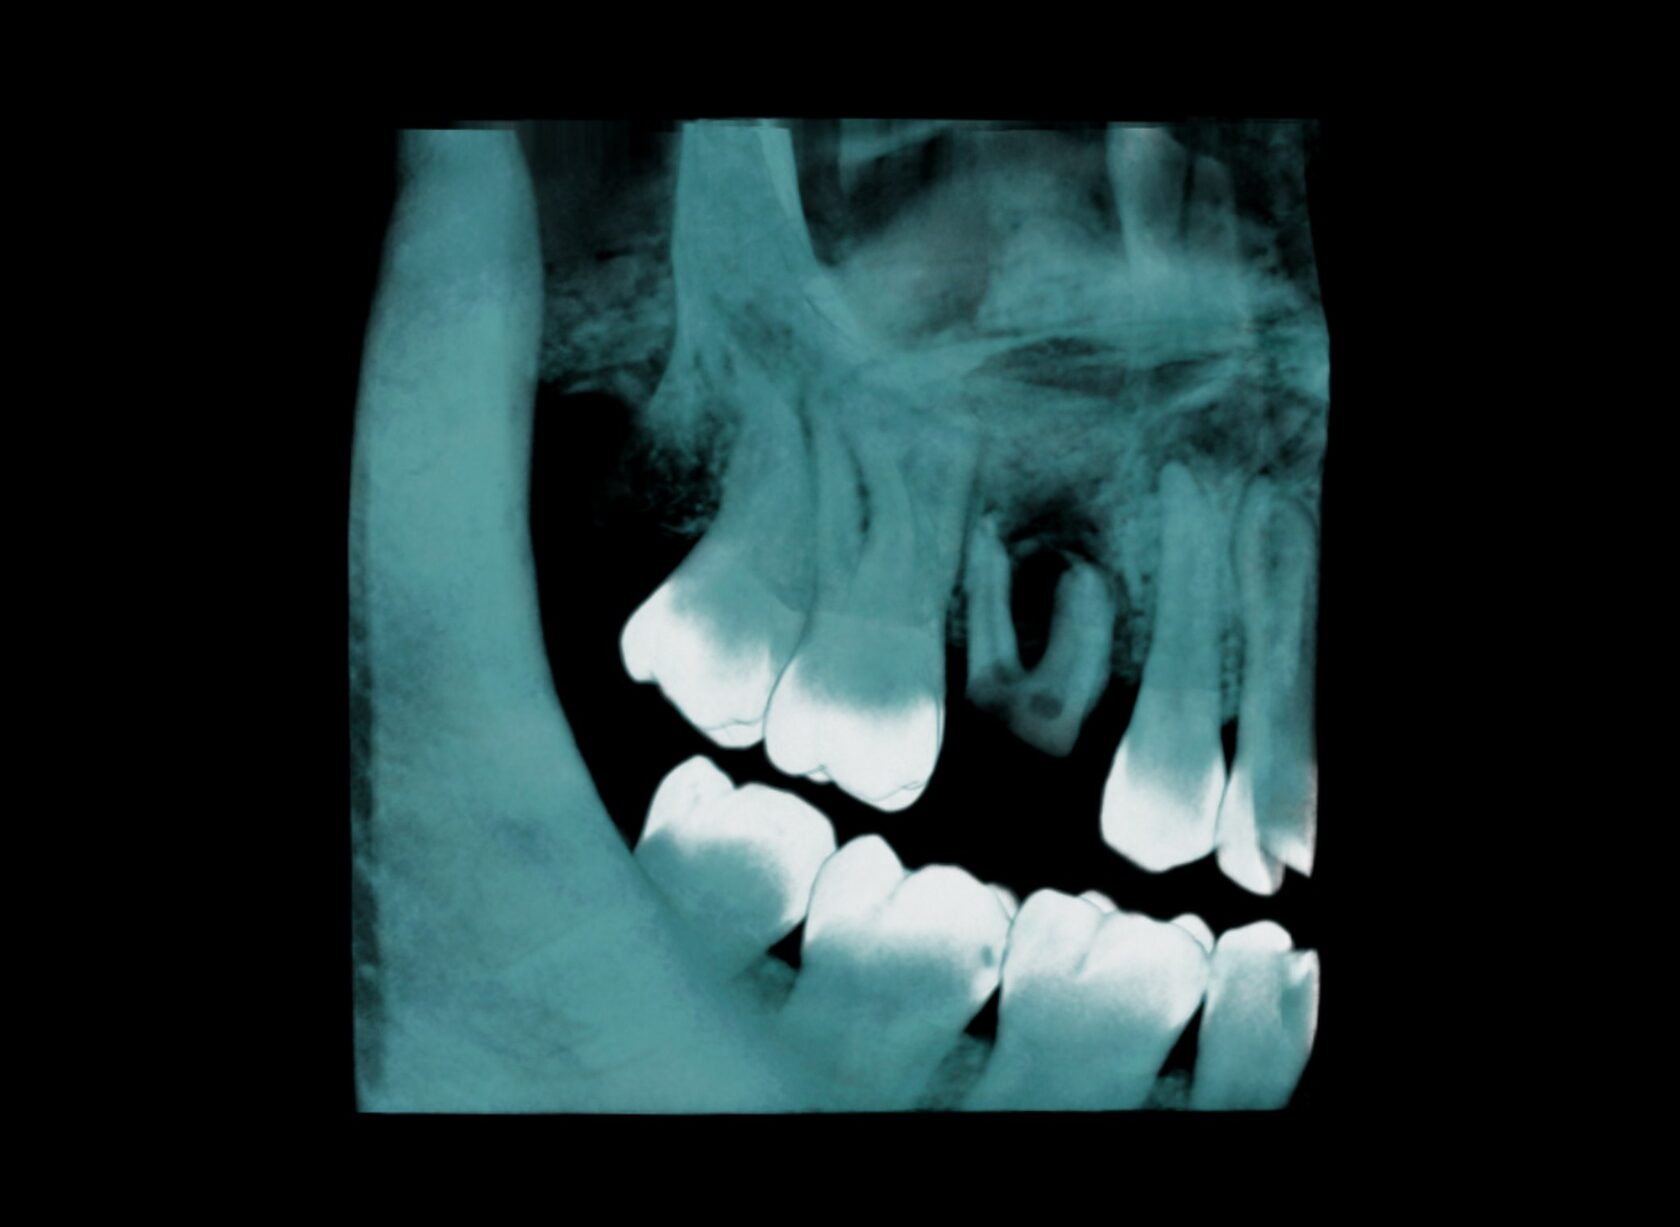

Скриншот каждого корня (канала). Подробное описание. Коронка, канально-корневая система, периапикальные ткани, пародонтальный статус. Скриншоты ВНЧС с измерениями. Описание положение головок, структуры, формы, размеров. Описание всех измененных структур ЧЛО (зубы, пазухи, кость).

Скриншот каждого корня (канала). Подробное описание. Коронка, канально-корневая система, периапикальные ткани, пародонтальный статус. Скриншоты ВНЧС с измерениями. Описание положение головок, структуры, формы, размеров.

Скриншот каждого корня (канала). Подробное описание. Коронка, канально-корневая система, периапикальные ткани, пародонтальный статус.

Скриншоты интересующей зоны\образования\группы зубов (до 5 зубов) и ее описание.